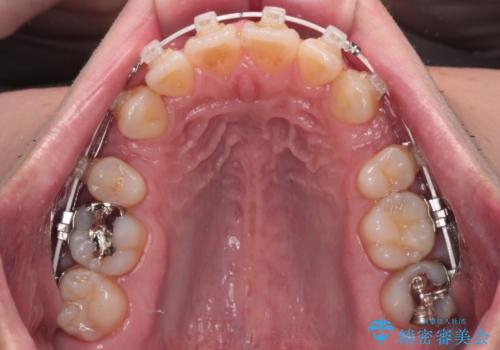

- 審美装置

なるべく目立たない装置が希望だったため、審美装置で治療を行いました。

左上はアンカースクリューを併用することでスムーズに抜歯スペースを閉じることができました。